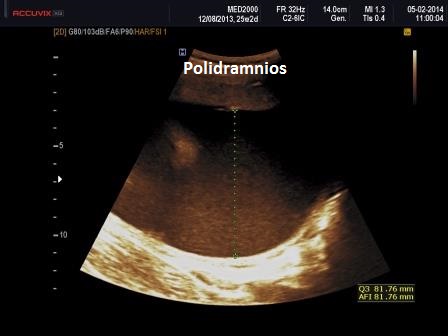

Polidramnios

Nel polidramnios la misurazione della tasca massima di liquido amniotico è superiore a 8 cm. e l'indice di liquido amniotico è superiore a 25 cm. La misurazione della tasca massima viene utilizzata per classificare il polidramnios in lieve (8-11 cm), moderato (12-15 cm) e severo (≥16 cm).

Esistono essenzialmente due cause principali di polidramnios: Ridotta deglutizione fetale e Aumento della diuresi fetale. Bisogna comunque considerare che il polidramnios nel 50-60% dei casi è idiopatico, quindi non se ne conosce la causa. La ridotta deglutizione fetale può essere causata da anomalie cerebrali (ad esempio anencefalia, malformazione di Dandy-Walker), tumori facciali, ostruzione gastrointestinale (come nell’ atresia esofagea o duodenale, ostruzione del piccolo intestino), disturbi polmonari compressivi (ad esempio versamenti pleurici, ernia diaframmatica, CPAM, CHAOS), gabbia toracica stretta conseguente a displasie scheletriche e sequenza ipo-acinesia-deformazione-fetale (dovuta alla compromissione neuromuscolare della deglutizione fetale). L'aumento della diuresi fetale può essere dovuta a diabete mellito materno e uremia materna (l’aumento di glucosio e di urea causano diuresi osmotica), circolazione iperdinamica fetale dovuta ad anemia fetale (es. isoimmunizzazione Rh o infezione congenita), tumori fetali e placentari (es. teratoma sacrococcigeo, corioangioma placentare) o sindrome da trasfusione feto-fetale (Fetal Medicine Foundation FMF).